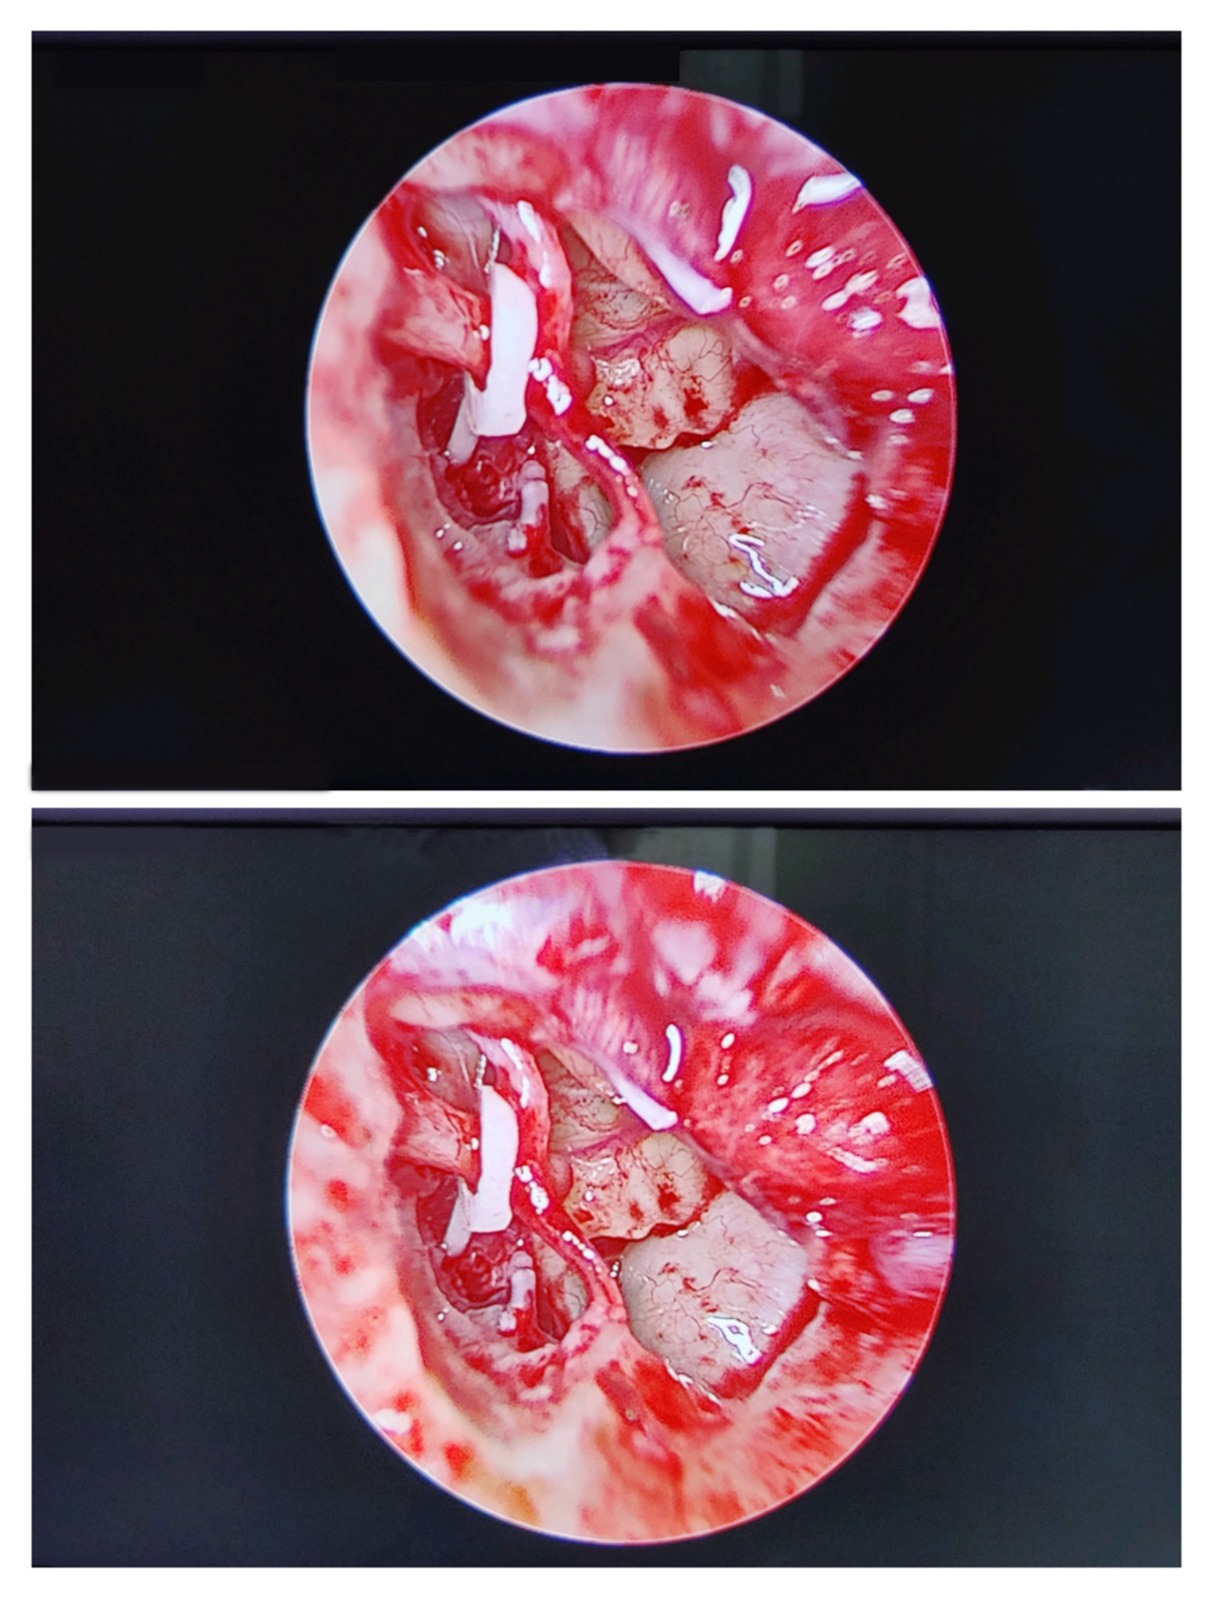

1. Tympanoplasty (Eardrum Repair Surgery)

Tympanoplasty repairs a perforated or damaged eardrum using advanced microscopic techniques.

It is recommended that you have:

- Hearing loss

- Recurrent ear infections

- Ear discharge

- Trauma-induced perforation

Benefits of Tympanoplasty

- Restores hearing

- Prevents repeated infections

- Improves ear function

- Strong long-term outcomes